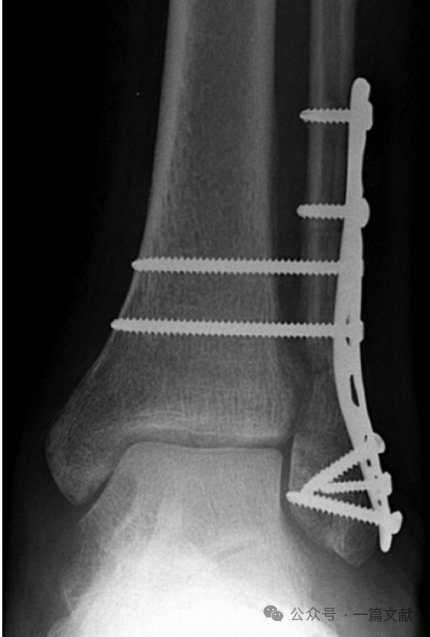

3,弹性固定:很多研究显示,相较于常规螺钉固定,弹性固定并没有明显优势。如下图,